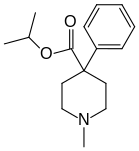

The first fully synthetic opioid was meperidine (later demerol), found serendipitously by German chemist Otto Eisleb (or Eislib) at IG Farben in 1932.[228] Meperidine was the first opiate to have a structure unrelated to morphine, but with opiate-like properties.[199] Its analgesic effects were discovered by Otto Schaumann in 1939.[228] Gustav Ehrhart and Max Bockmühl, also at IG Farben, built on the work of Eisleb and Schaumann. They developed "Hoechst 10820" (later methadone) around 1937.[230] In 1959 the Belgian physician Paul Janssen developed fentanyl, a synthetic drug with 30 to 50 times the potency of heroin.[211][231] Nearly 150 synthetic opioids are now known.[228]

Phenylpiperidines

- Pethidine (meperidine)